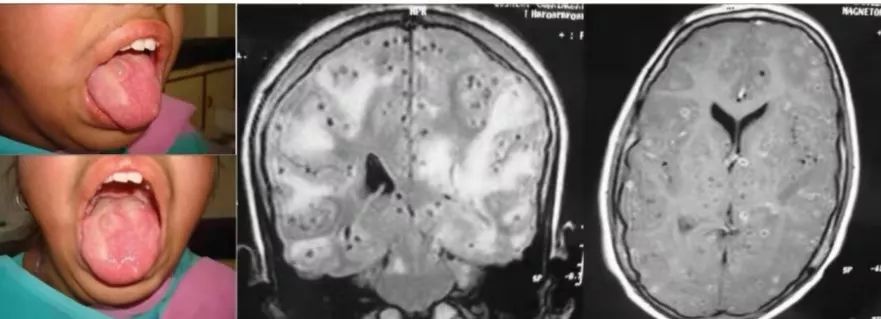

14岁的女孩,舌部有多处软肿。认知能力下降,出现了躁动症。精神运动迟钝,学习成绩下降。MMSE评分为22/30。

答案:脑囊虫病。

患者的舌体显示多发性囊性结节性肿物,触诊边缘不清的软结节,无压痛。核磁共振显示多发性肉芽肿,提示脑囊虫病的不同时期。少数肉芽肿也显示出偏心的头节。组织病理学检查显示囊虫病幼虫的导管样内陷,由均质膜衬里的幼虫组成。脑实质型脑囊虫病MRI较有特征,多为圆形囊性病变,2-8mm大小,其内可见偏心的附壁小点状影,代表囊虫头节。脑囊虫存活期水肿轻。增强扫描囊壁可强化或不强化。囊虫死亡时,头节显示不清,周围水肿加剧,占位明显,强化环厚度增加。此时可见“白靶征”,即T2WI囊液及周围水肿呈高信号,而囊壁与囊内模糊不清的头节呈低信号,低信号为囊虫逐渐纤维化、机化和钙化,含水量减少,氢质子密度减低所致。